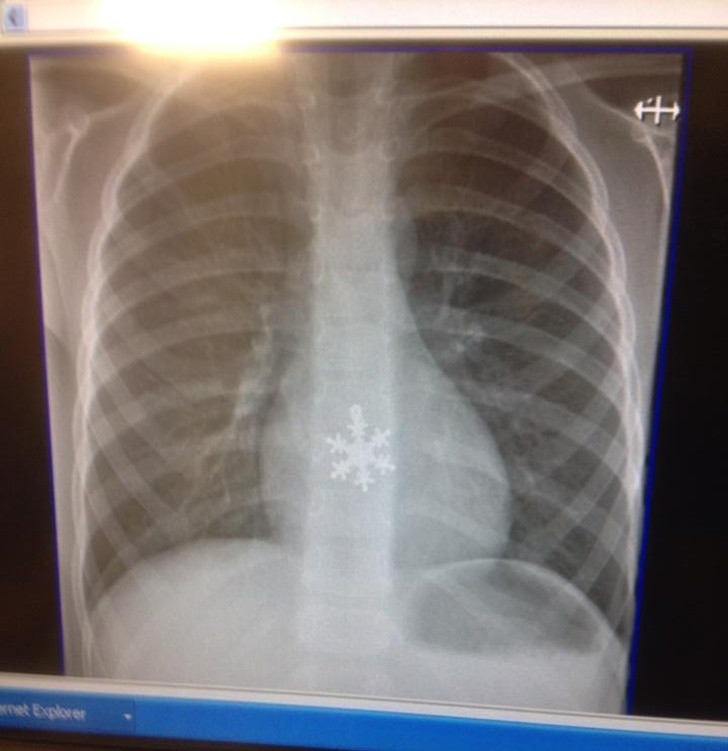

Ljudje smo resnično čudna bitja in se nam lahko zgodijo neverjetno bizarne stvari. Ti rentgenski posnetki bodo šokirali tudi tiste, ki mislijo, da so videli že vse.

Rentgen je eden najboljših izumov človeštva in v nekaterih situacijah je nepogrešljiv. Še posebej zato, ker se velikokrat zgodi, da ljudje, še posebno otroci, požirajo predmete, ki niso del dnevne prehrane. Da ne omenjamo psov, ki poskušajo prežvečiti vse, kar vidijo, in tako velikokrat pogoltnejo neprimerne stvari.

Radiologi so tako že precej navajeni, da na rentgenskih posnetkih vidijo čudne stvari in nekatere izmed teh, ki smo jih za vas zbrali v galeriji, jih sploh niso presenetile. Tukaj je 15+ odštekanih in na trenutke šokantnih rentgenskih posnetkov.